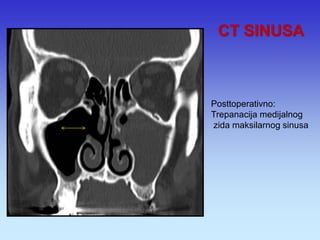

CT SINUSA

Posttoperativno: Trepanacija medijalnog zida maksilarnog sinusa